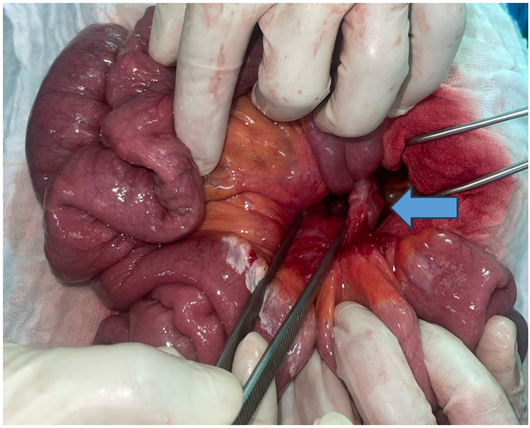

Careful reduction of the hernia contents was achieved, consisting of approximately 2.30 meters of viable small bowel. The hernia defect was closed using absorbable sutures.

Figure 4: Intraoperative view after complete reduction of the hernia contents.